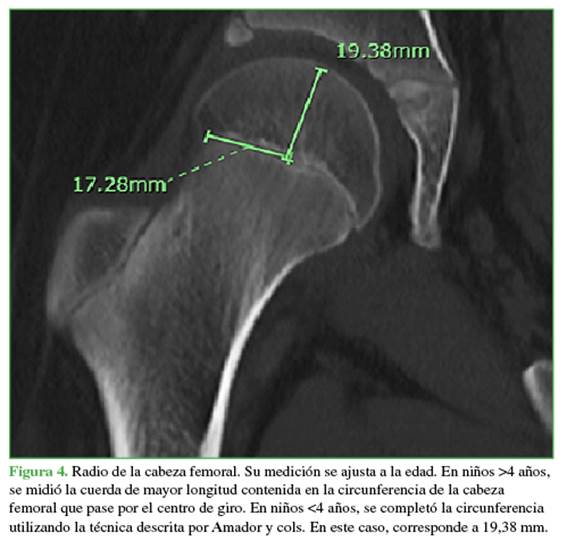

En los pacientes >4 años, el desplazamiento femoral fue la distancia ortogonal entre el centro geométrico de la cabeza femoral y el eje de la diáfisis del fémur proximal (Figura 1).

En los pacientes de 4 años o menos, se utilizó el método descrito por Amador y cols. para ubicar el centro de la cabeza femoral: se dibujó una secante que conecta los puntos más distales de las curvaturas medial y lateral metafisarias y una perpendicular en el centro de esta secante. El centro de la cabeza femoral es el punto sobre esta perpendicular que se ubica a la distancia desde la metáfisis descrita por Amador y cols. según la edad.9 El ángulo cervico-diafisario es el ángulo entre el eje del cuello femoral y el eje diafisario femoral en todos los casos (Figura 2).10

Se incluyó a 40 pacientes (promedio de edad, 9 años; rango de 6 meses a 18 años). El desplazamiento femoral muestra un crecimiento lineal en el tiempo con una tendencia a aumentar aproximadamente 1,96 mm al año hasta los 12.5 años, con un posterior aplanamiento de la curva y un aumento en el desplazamiento de 1,2 mm entre los 12.5 y 16 años (Figura 5). Respecto a la longitud del cuello femoral, la tendencia de crecimiento es constante, a una velocidad de 1,95 mm por año (Figura 6).